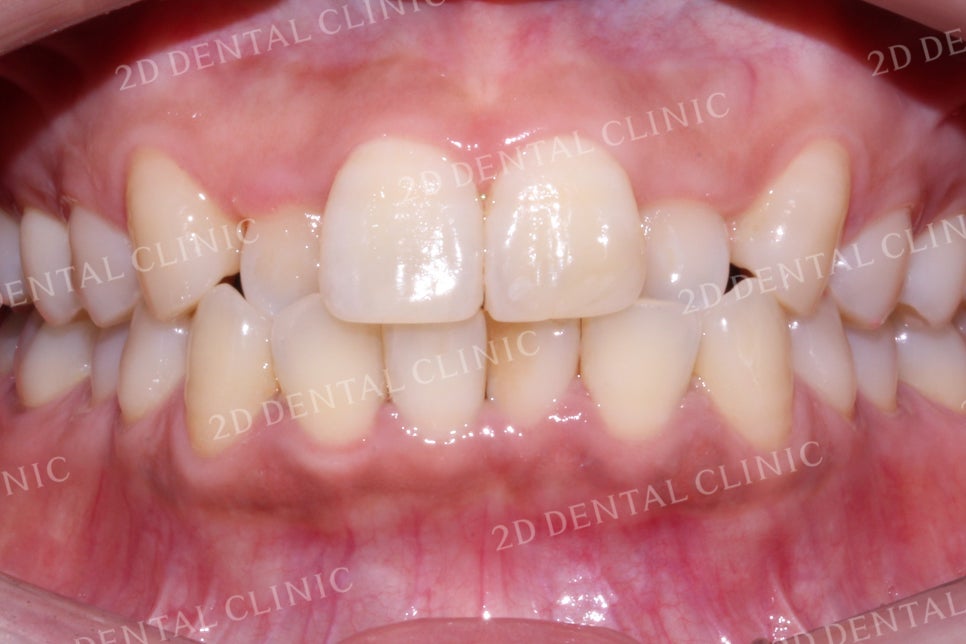

미소 시 치아의 상태를 보시면

전치부의 치아들이 삐뚤삐뚤하고

상악 측절치가 반대로 물리고 있었습니다.

교정 후 삐뚤삐뚤하던 치아의 크라우딩이

많이 사라졌고, 상하악의 정중선도

가지런하게 맞춰졌습니다.

또한 반대로 물리고 있었던

측절치가 정상적인 교합으로 바뀌며

바른 교합 상태를 갖추게 되었습니다.